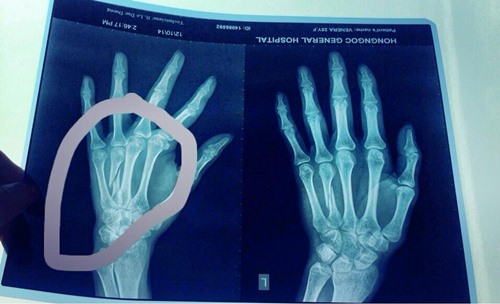

Nữ người mẫu Venera chia sẻ bức ảnh cô chụp X- Quang về ngón tay bị gãy.

Bàn tay cô phải băng bó khiến cô mất nhiều show diễn.